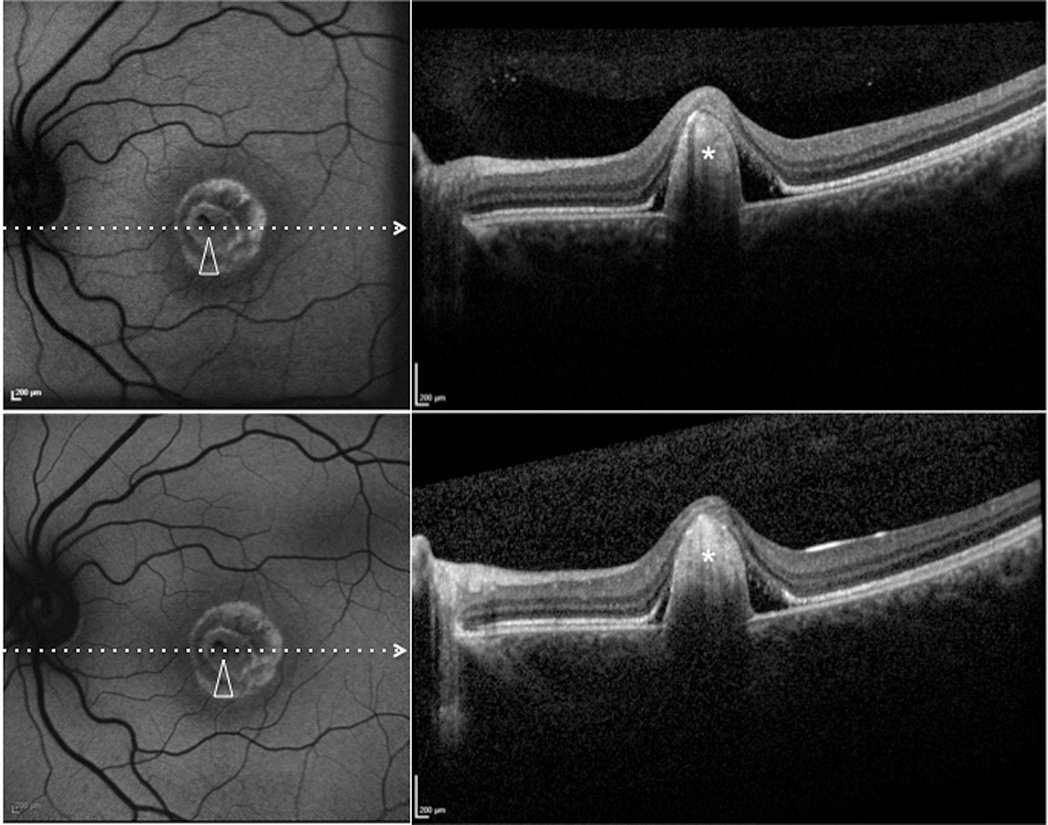

Figure 9. Patient #6. Blue fundus autofluorescence (FAF) and spectral-domain optical coherence tomography (SD-OCT) reveal the right

eye affected with fibrotic lesion at both study entry and last follow-up visit (24 months later). At study entry (top left

and top right panels), blue FAF frames show central (arrowhead) reduced autofluorescence (with some residual dispersed autofluorescent

material), and SD-OCT shows a prominent highly hyperreflective thickening at retinal pigment epithelium level, inducing marked

anterior bulging, accompanied by diffuse loss and thinning of the sensory retina (asterisk). Blue FAF and SD-OCT findings

appear unchanged at the last follow-up visit (bottom left and bottom right panels). Note the presence of a hyperautofluorescent

ring.